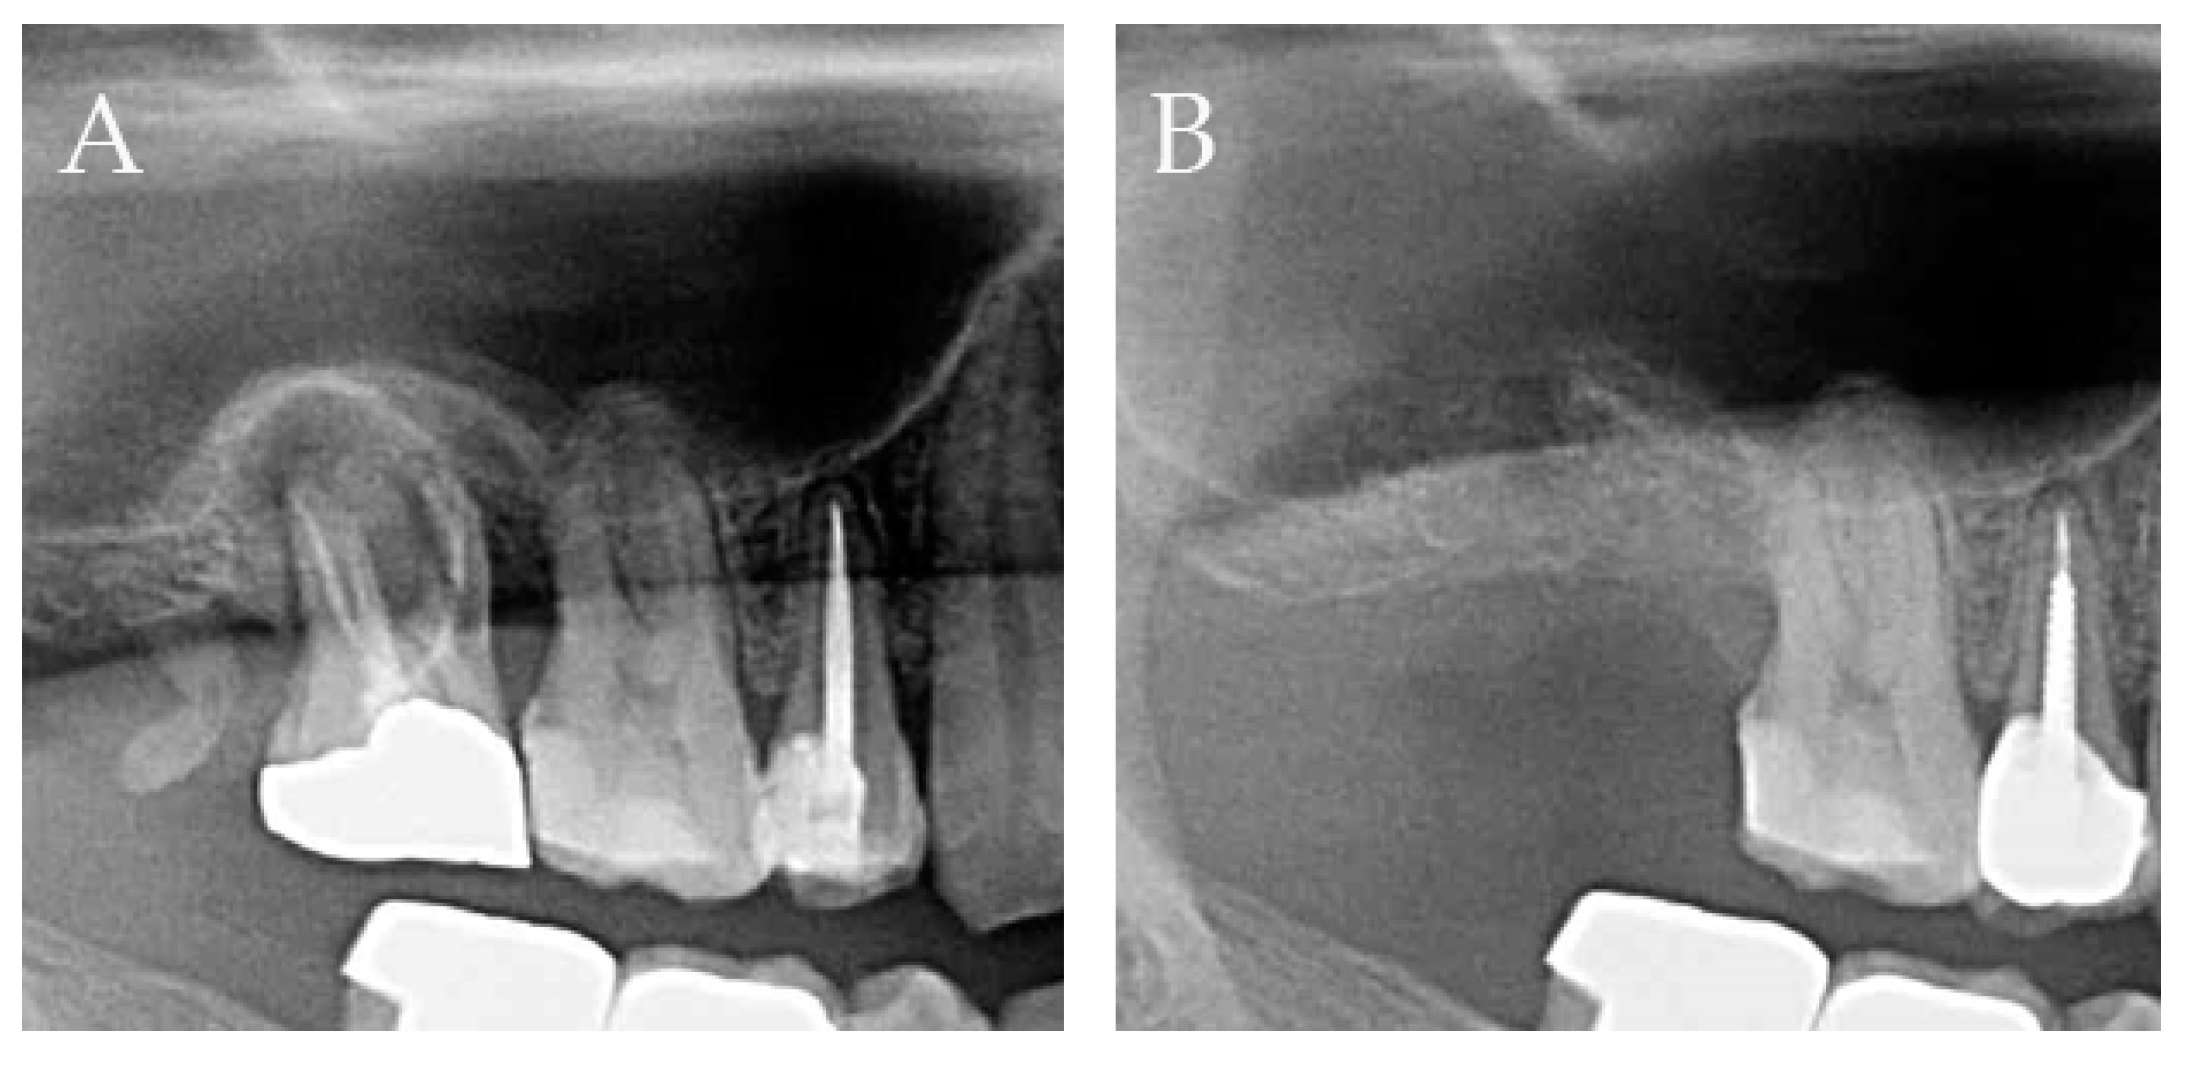

3.3. Radiographic Measurement

| Time of Measurement | Average Radiographic Change in Alveolar Bone Height (mm) |

|---|---|

| Preoperative | 0 |

| One month after extraction | −0.02 ± 1.20 |

| Two months after extraction | 0.05 ± 1.14 |

| Three months after extraction | 0.11 ± 1.20 |